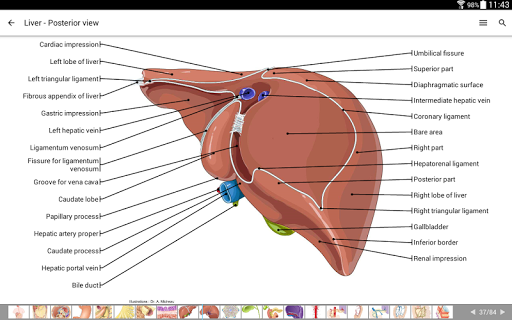

- وحدة جديدة للمشتركين: أطلس تشريح الشجرة الصفراوية داخل وخارج الكبد ، القناة الصفراوية المشتركة (CBP ، Ductus choledocus) ، المرارة ونظام الأقنية البنكرياسية (قناة Wirsung) على التصوير بالرنين المغناطيسي (MR cholangiopancreatography)